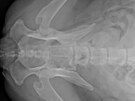

Rentgenový snímek ukazuje, jak šíp pronikl do těla. Šíp prošel podél páteře až k lopatkám. Střelec tvrdil, že chtěl psa jen zastrašit, ale šíp z kuše ho zasáhl do zadní...